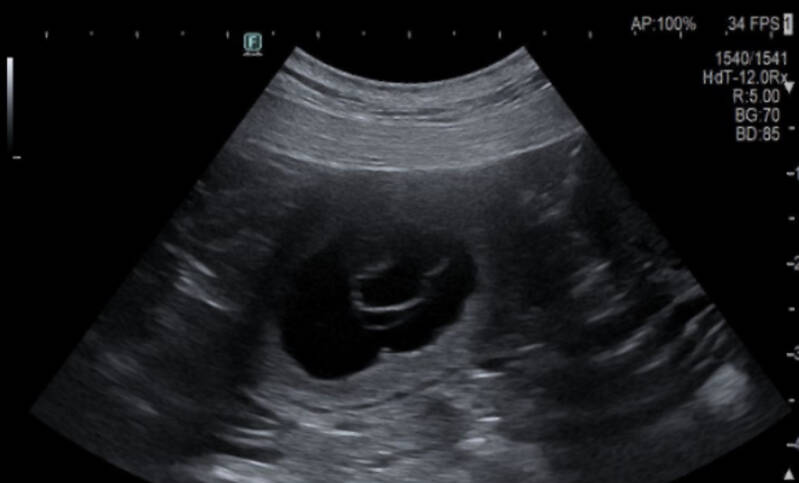

Wilma beim Ultraschall am 18.02.2026 -> Wilma ist trächtig